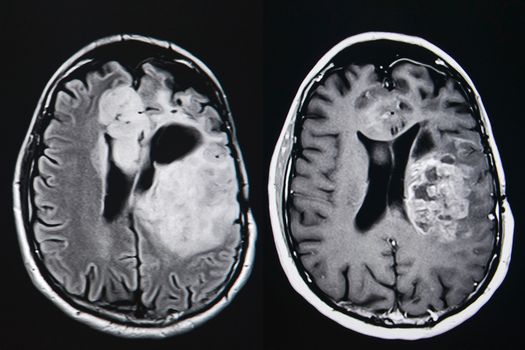

I was referred to a specialist when hormone levels came back raised and have since had a brain MRI which has determined that I do in fact have a pituitary adenoma; a noncancerous tumour of the pituitary that just sort of sits there, producing prolactin, a hormone that leads to my initial symptoms. I was so relieved, I can’t even begin to describe it. But what does that say about the reality of being a woman with a womb in Ireland? What does it say when I can throw my hands up in the air and say “I’d rather be sick than pregnant”?

The tumour is currently tiny, can largely be treated with medication, and will need monitoring throughout my life. If treatment doesn’t go to plan, it’s possible to shrink it with radiation, and in the highly unlikely case that it grows, it can be removed with a routine surgery. I’ve taken the liberty of naming him Dave, because he’s benign, and have you ever met a malignant Dave? It may seem strange to be relieved by a rare medical diagnosis, but this the reality of Ireland if you are a woman who doesn’t want to be pregnant.There are a variety of healthcare options on offer to me, many of which are covered by my health insurance. I have been presented with a wealth of information about exactly what’s going to happen and what is available to me through the process. If I had been pregnant, I would have had two options; become a mother, or become a mother while someone else becomes the parent of my child. I simply wouldn’t have had the money to go to the UK to have an abortion, and if somehow I had made it over, I would have been expected to come back and be quiet about it.